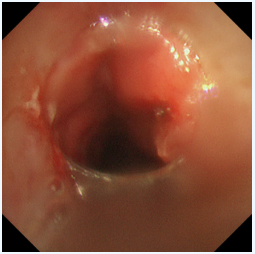

两种技术优势互补,相得益彰,在微小创伤的前提下,实现了对复杂气道狭窄的最大化疏通。

此例高难度气道狭窄激光联合冷冻治疗的成功,充分体现了我院呼吸内科团队在处理复杂气道疾病方面“精准化、微创化、多学科一体化”的重大突破。王剑主任指出:对于喉癌术后、气管插管或切开后遗留的气道狭窄,介入肺脏病学技术提供了全新的微创解决思路。激光与冷冻的联合应用,既能快速解除危急,又能追求长期疗效,为广大慢性气道疾病患者提供了更安全、高效的诊疗选择。未来,我院呼吸内科将紧跟新近技术发展,持续提升专业内涵,为呼吸系统疾病患者个性化治疗方案提供更多选择,帮助患者改善症状,促进康复,提高生活质量。